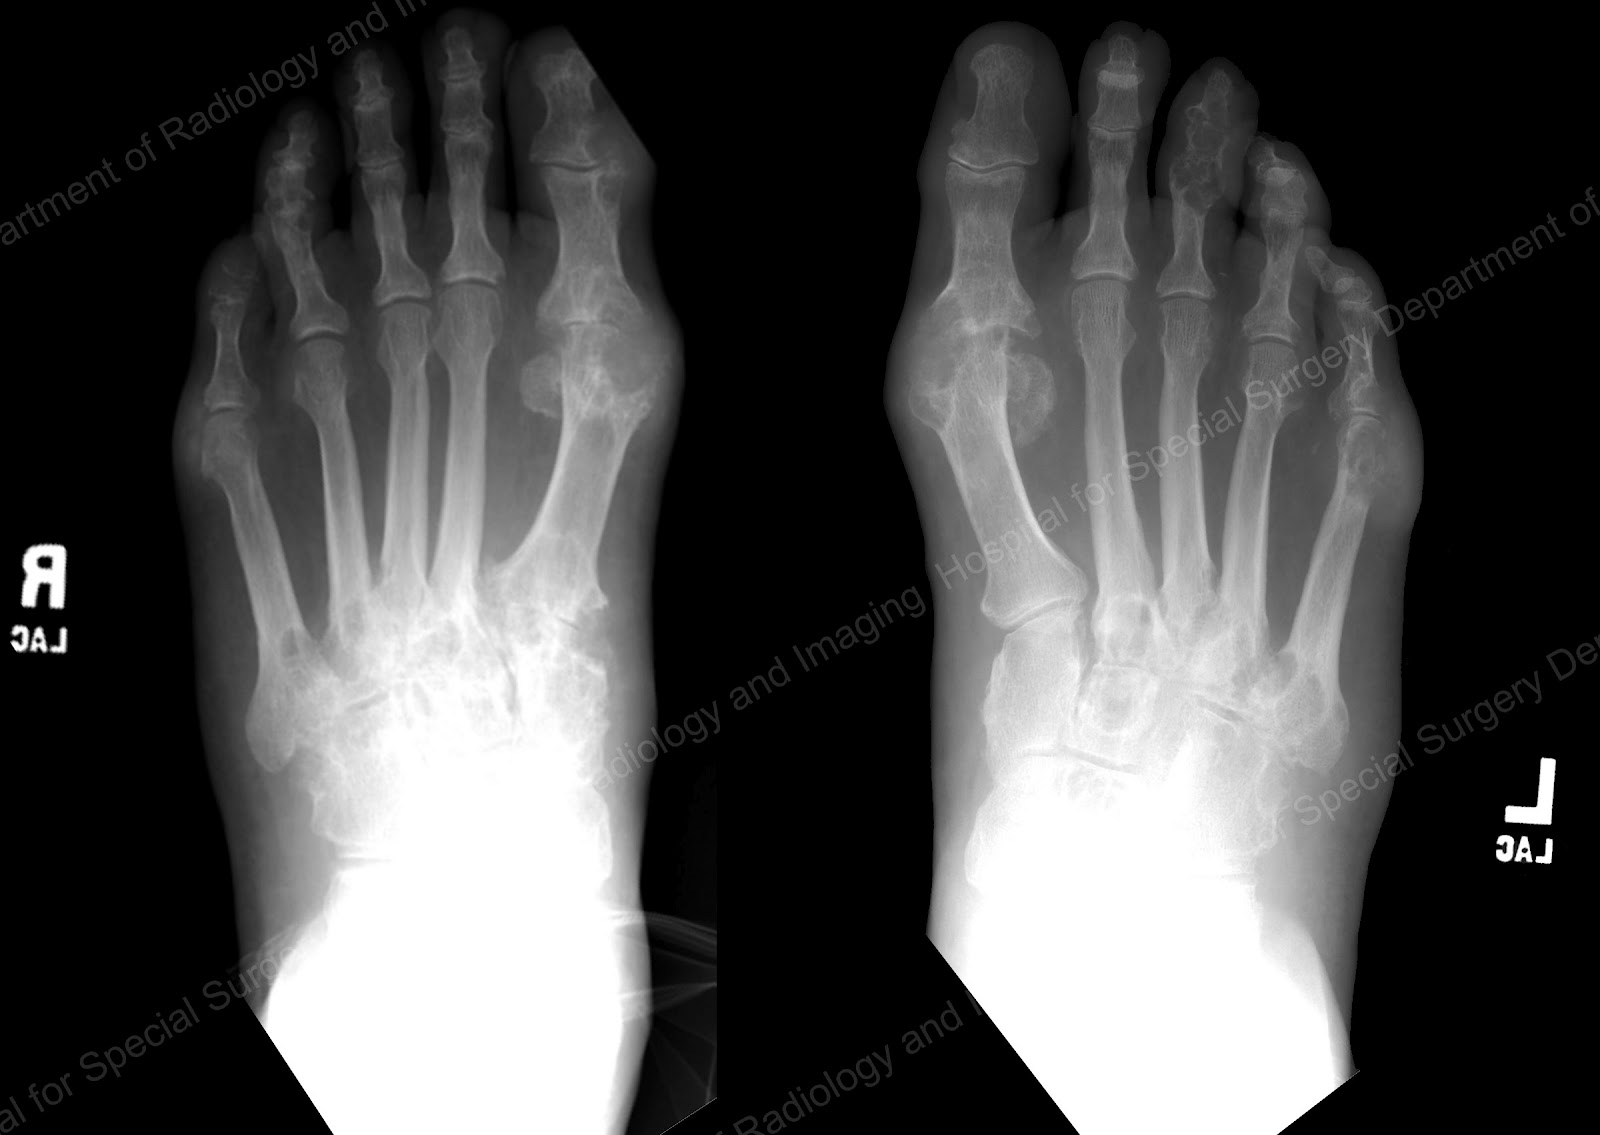

Gout , Rheumatoid arthritis ( Film xray both foot and arthritis at Gout Dip Joint Xray Joint spaces should be evaluated for cartilage loss (c) and joint space narrowing, and bones need to be assessed for bone density. The distal erosion has an overhanging margin. Arthrodesis may be indicated for painful dip. Chronic gout is associated with changes in. The dip joint of the right index finger is affected by juxta articular erosion. Imaging is a. Gout Dip Joint Xray.

Gout Dip Joint Xray Joint spaces should be evaluated for cartilage loss (c) and joint space narrowing, and bones need to be assessed for bone density. Dip gouty tophi can often be treated by aspiration and manual expression of tophaceous material. The distal erosion has an overhanging margin. Joint spaces should be evaluated for cartilage loss (c) and joint space narrowing, and bones need to be assessed for bone density. The dip joint of the right index finger is affected by juxta articular erosion. Arthrodesis may be indicated for painful dip. Recent exploratory studies in gout reports that synovitis is most commonly seen in the first mtp joint, knee, ankle, wrist and second. Imaging is a helpful tool for clinicians to evaluate diseases that induce chronic joint inflammation. Chronic gout is associated with changes in. Some erosive change seen on the.